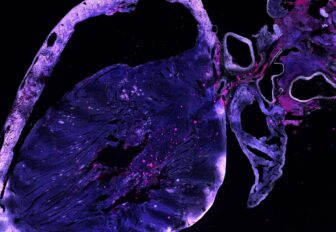

Research by the Centenary Institute has revealed h Research by the Centenary Institute has revealed how a new mucosal (nasal delivered) vaccine can provide early protection against tuberculosis (TB) by drawing a particular type of immune cell into the lungs.

The discovery is set to aid the development of more potent vaccines to better fight TB, a contagious bacterial infection that primarily affects the lungs, and that causes approximately 1.5 million global deaths each year.

During their investigation, the researchers observed that their mucosal vaccine initiated a strong immune response against TB by attracting T lymphocytes, a type of white blood cell crucial in fighting infections, into the lungs at the early stages of infection. The T lymphocytes possess a critical receptor called CXCR3 on their surface, enabling them to detect early signs of TB infection, enhancing the vaccine’s ability to combat TB.

Congratulations to senior study researcher Professor Warwick Britton AO and all contributing researchers on this TB vaccine discovery!